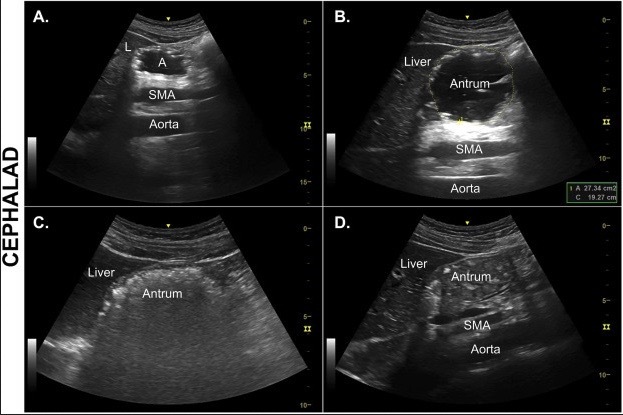

20.2 The structure labelled A shows (gastric ultrasound image shown)

a. Empty stomach

b. Full stomach with Solids

c. Full stomach with liquids and Air

d. Gall Bladder

e. Abdominal Aorta